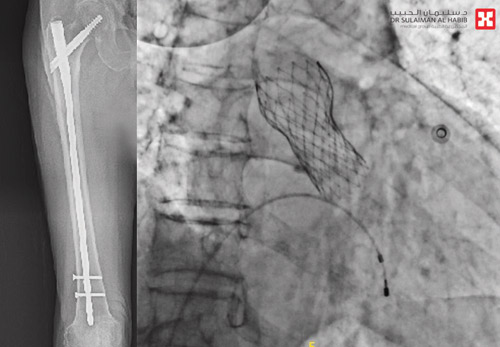

وقال د. فيصل أنه على الفور تم إجراء عملية عاجلة للمريض بالقسطرة استغرقت 60 دقيقة تحت التخدير الموضعي، وتم فيها إستبدال الصمام الأورطي، وأكدت الفحوصات بعد ذلك تحسن المؤشرات الحيوية للمريض واستعادة العمل الوظيفي للقلب، ونقل بعدها إلى جناح التنويم وهو بصحة جيدة.

من جهته قال د. أنور الربيعة استشاري ورئيس قسم العظام والعمود الفقري، أن الفريق الطبي استكمل الخطة العلاجية بعد يومين من عملية القسطرة، حيث أجريت للمريض عملية دقيقة استغرقت ساعة ونصف تحت التخدير الموضعي، وتم فيها إصلاح كسر عظمة مفصل الفخذ، وتكللت جهود الفريق الطبي بالنجاح التام وخرج المريض من المستشفى بعد 5 أيام وهو بحالة صحية جيدة.